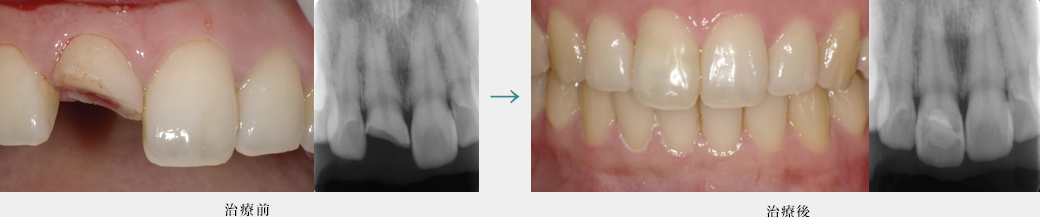

ダイレクトボンディングによる健全な歯質を温存した虫歯治療(前歯)

健全な歯質は削らず物性に優れた樹脂を詰めています